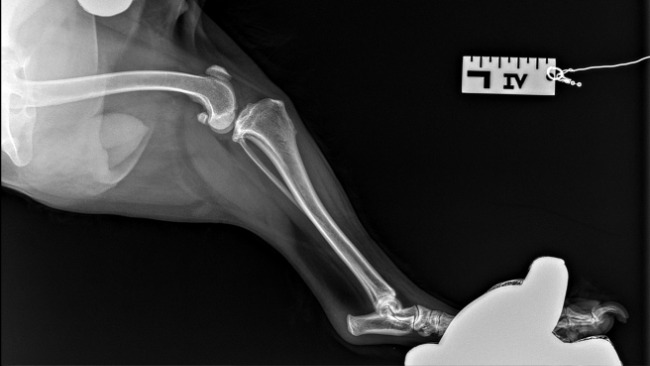

Jestem Melania, psiakiem, który ma 4 lata i 3 miesiące, od pewnego czasu mam problem z chodzeniem, teraz nie jestem w stanie wchodzić po schodach, spacerować, biegać za piłeczka ani normalnie funkcjonować. Leżę cały czas, śpię i staram się nie wychodzić. Moja Pani mówi ze wszystko będzie dobrze, ze będę jeszcze kiedyś szczęśliwym, pełnym energii pieskiem. Teraz potrzebujemy wsparcia finansowego, ponieważ leczenie i dotychczasowe badania sporo nas kosztowały. Zbieraliśmy pieniądze na rezonans, który po konsultacji z doktorem w klinice Auxilium okazał się niepotrzebnym i dodatkowym dla mnie stresem. Dziś miałyśmy termin tego badania DIAGNOZA NIESTETY BYŁA NAJGORSZA - będzie potrzebna OPERACJA STAWÓW (ZERWANIE WIĘZADŁA KRZYŻOWEGO). Został wykonany mi test kompresyjny, który okazał się obustronnie dodatni oraz u mnie wystąpiła reakcja bólowa podczas jego wykonywania. Dodatkowo wykonano mi dwa zdjęcia RTG samych stawów (załączamy je). Obustronnie prawidłowe reakcje korektury kończyn piersiowych i miedniczych, prawidłowe odruchy kolanowe, piszczelowe i cofania kończyn. Zwróciliśmy się z zapytaniem do administratora portalu pomagam.pl czy dotychczasowe pieniążki uzbierane na rezonans możemy przepisać na zbiórkę operacji i oczywiście wyrazili zgodę. Po prostu przekształcamy tę zbiórkę. Chcemy teraz Was - ludzi o wielkim, ciepłym serduszku poinformować o stanie Melanii. Wcześniej pisaliśmy, że może być tak, "że przejdę poważną operację, po której dopiero dojdę do siebie, ale moja Pani powiedziała, że nigdy się nie poddamy i zrobimy wszystko, żebym była zdrowa. Jestem jeszcze młodziutka i całe życie przede mną dlatego będę bardzo wdzięczna za każdą formę pomocy". Dziś jesteśmy pewne, że operacja odbyć się musi, stawy które mogą zostać mi wstawione kosztują 2500 zł za jeden, co w moim przypadku trzeba pomnożyć przed dwa. Wybór tej metody, czyli pozwoli mi na swobodne poruszanie i wykonywanie podstawowych funkcji życiowych. Droga do diagnozy była dla nas naprawdę długa i kosztowna. Jest wyczerpana, teraz marzę o tym, żeby moje tylne łapki już dłużej nie sprawiały mi tyle bólu :( .Pani mówi, że pozostaje nam czekać, czy uda nam się uzbierać pieniążki na moją operację? Doktor powiedział, że dwa tygodnie się czeka od zarezerwowania terminu ;(